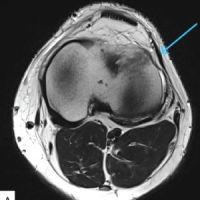

During the arthroscopic portion of the surgery in May 2023, a grade 1 chondral lesion on the lateral patellar facet was identified according to the Outerbridge classification, and lateral retinacular release was performed. During the second part, the tibial tuberosity (TT) was medialized by 1 cm and secured with two 4.5 mm lag screws, achieving a TT-TG distance up to 10 mm in the final measurement (Fig. 1).